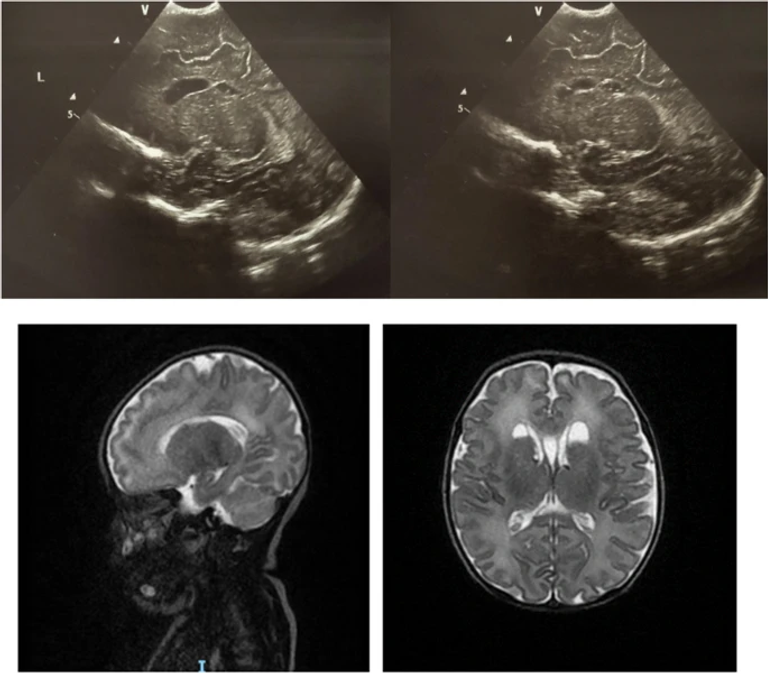

SARS-CoV-2’s potential consequences on the developing brain are still unknown. The aim of this study was to describe cranial ultrasonographic (cUS) findings in a population of newborns exposed to SARS-CoV-2 born at San Marco Hospital in Catania.

We enrolled 139 exposed newborns (62 females, 77 males with median gestational age 38.4 ± 1.9 W and median weight at birth 3142.8 ± 594.4 g) and 139 unexposed newborns (60 females, 79 males with median gestational age 38,9 ± 1.3 W and median weight at birth 3230 ± 336 g). cUS abnormalities were found in 32 exposed patients (23%) and in 23 (16.5%) unexposed patients. A statistically significant difference was found in the incidence of minor intracranial abnormalities (p 0.036) between exposed and unexposed patients and between newborns exposed during pregnancy and unexposed patients (p 0.016).

In our experience, the incidence of minor intracranial abnormalities was higher in SARS-COV-2-exposed newborns. Our results must be taken with caution and need further confirmation in larger studies but suggest to consider performing cUS at birth in newborns exposed to SARS-CoV-2 in research contexts.